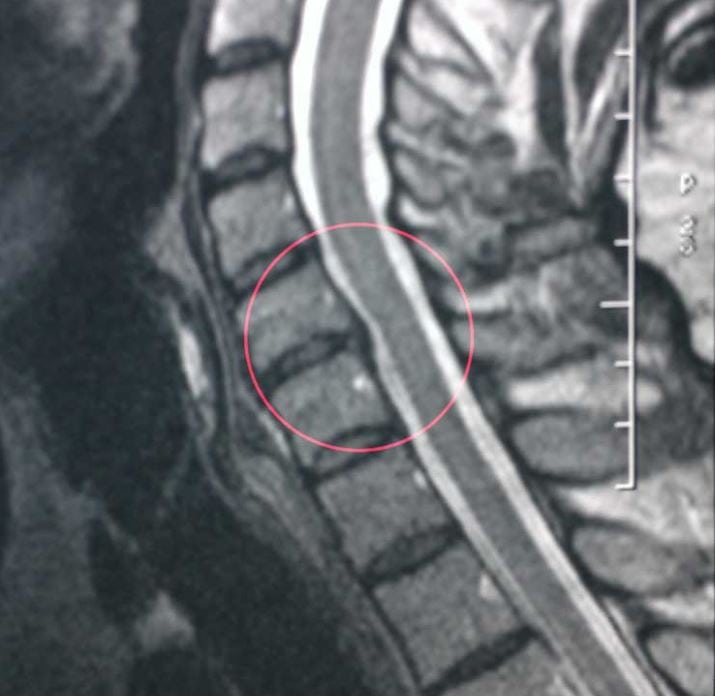

Врач-невролог весело сказал, что это типичные признаки шейного остеохондроза и порекомендовал пройти МРТ. Снимок МРТ показал наличие 4-х протрузий в шейном отделе позвоночника.

МРТ.

Связано это с дегенеративными изменениями хрящевого диска. Кровеносные сосуды шейного отдела позвоночника защемляются, что нарушает кровообращение. Головной мозг страдает из-за недостаточного снабжения кислородом, и слух обостряется, улавливая тот шум, который не должен. А исходит он от нервных клеток, лишенных «мозговых сигналов». Издавая собственные непрерывные сигналы, они заполняют этот пробел.